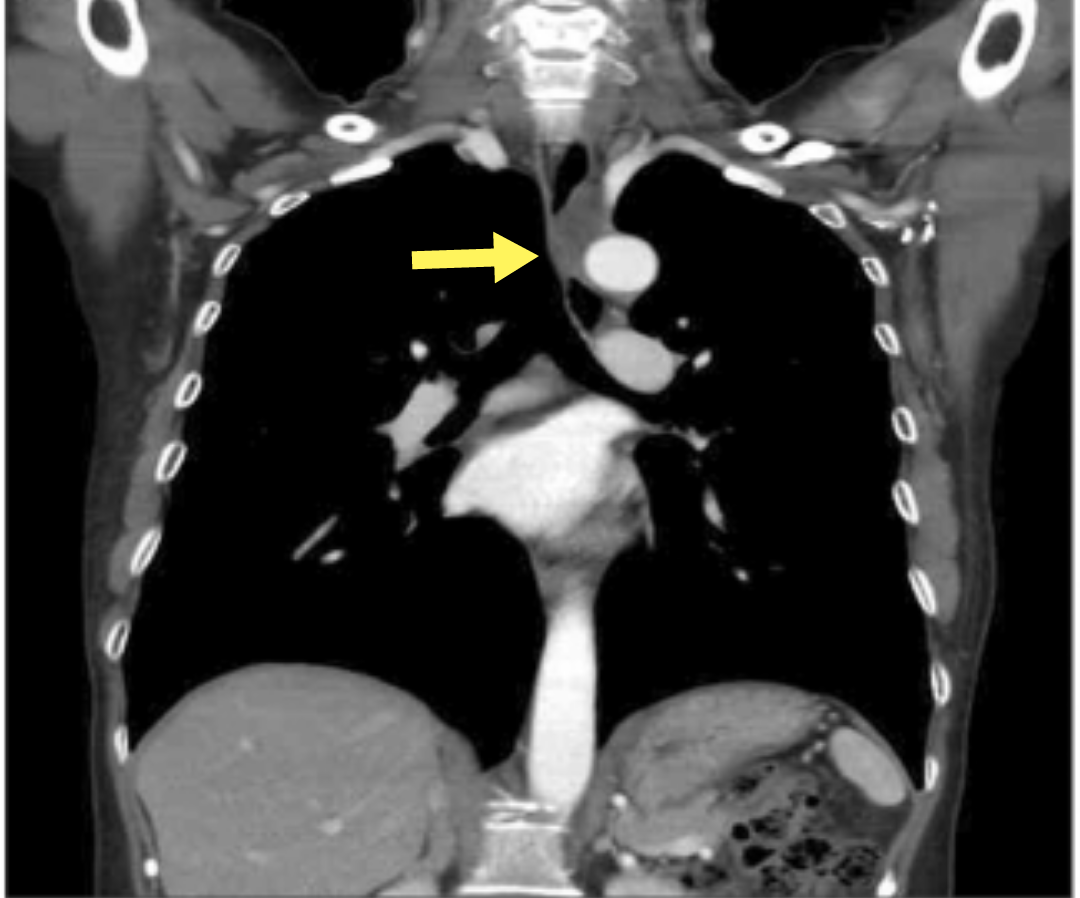

【病例】纵隔巨大支气管源性囊肿1例ct影像表现

纵隔囊肿